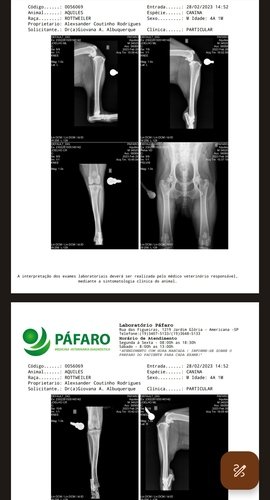

Meu papai logo me socorreu e me levou ao medico veterinário, me medicaram e cuidaram muito bem de mim como sempre fazem. Mas depois disso não fui mais o mesmo fui perdendo o movimento da minha perninha direita, meu papai vem fazendo de tudo para me ajudar e cuidar de mim. Faz meses que venho emagrecendo muito, pois não consigo comer pois sinto muita dor na minha perna e quadril. Meu papai me levou para fazer exames mais profundos e não teve boas notícias, DESCOBRIRAM QUE ESTOU COM DISPLASIA COXOFEMORAL, E RECENTEMENTE FUI DIAGNOSTICADO COM UM POSSÍVEL CÂNCER . Sinto muita dor, perdi muito Peso 16kilos estou muito triste e cansado. Descobri que se eu deitar encostado com as perninhas na parede amenizo minha dor. Por favor me ajude a voltar distribuir amor. Descobriram que não posso mais fazer cirurgia para cuidar da minha displasia, pois possivelmente um câncer está se desenvolvendo e tenho que fazer quimioterapia e tratamentos . Obrigado por nos ajudar quer ver meus exames e minha situação siga o perfil do meu papai lá no Instagram @alexsanderrcoutinho